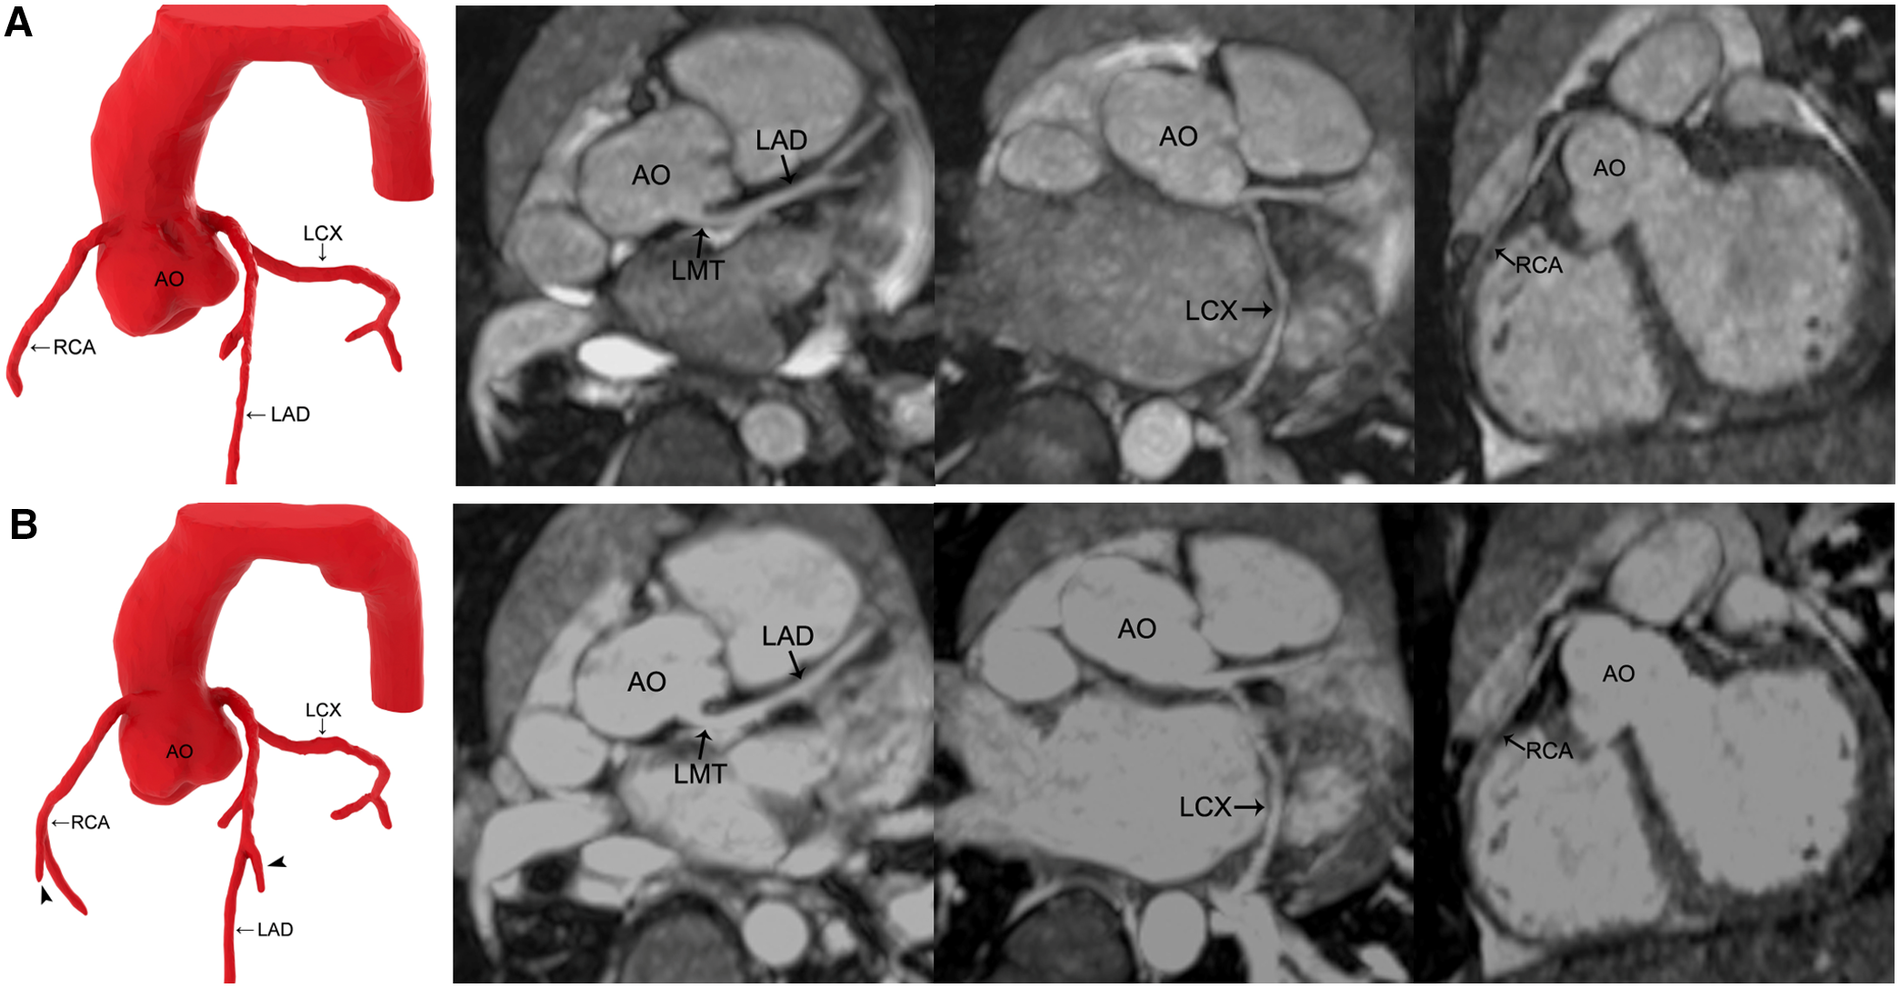

Figure 2

MR coronary angiography in a 3-year-old boy. (A) Precontrast imaging. (B) Postcontrast imaging. Compared with noncontrast-enhanced MR coronary angiography, the three dimension reconstruction image of MR coronary angiography after applying gadolinium-DTPA reveals more coronary artery side branches (arrowhead). Maximal intensity projection images show that the signal-to-noise ratio and contrast-to-noise ratio of all the coronary arteries increase after the application of gadolinium-DTPA, but the image quality is not improved significantly. AO, aorta; LMT, left main trunk; LAD, left anterior descending coronary artery; LCX, left circumflex coronary artery; RCA, right coronary artery.

The SNR and CNR of all the vessels in group 1 and group 2 and the LCX and RCA in group 3 improved after contrast agent injection (P < 0.05), whereas LMT and LAD remained unchanged in group 3 (P > 0.05) (Tables 4, 5) (Figures 2, 3).